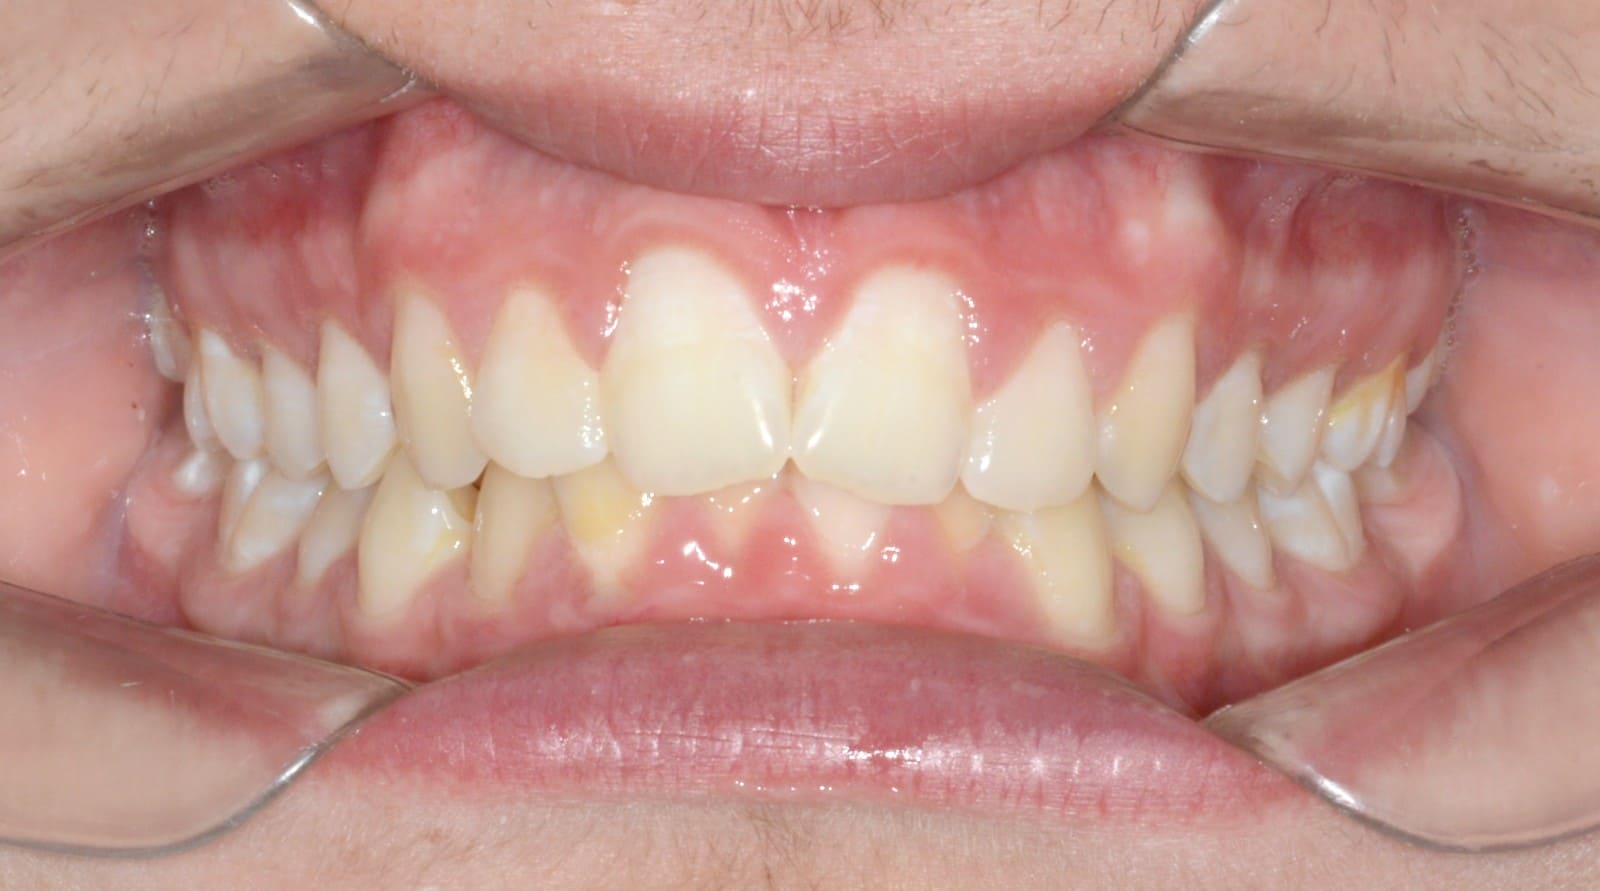

Final

- Class I relationship achieved

- Functional canine guidance on both sides

- Normal overjet and overbite achieved

- Significant improvement of overbite

- Significant improvement of overjet

- Proper axial inclination of incisors

- Curve of Spee leveled

- Arches aligned and coordinated

- Arch form improved

- Aesthetic smile line was achieved

- All treatment goals were achieved case

- Harmonic arches were achieved